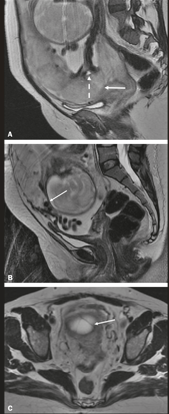

O Espectro do Acretismo Placentário

Em pacientes com Cesárea Anterior + Placenta Prévia, o risco de acretismo (invasão do miométrio pela placenta) é altíssimo.

- Diagnóstico: USG com Doppler ou Ressonância Magnética (principalmente para placenta posterior).